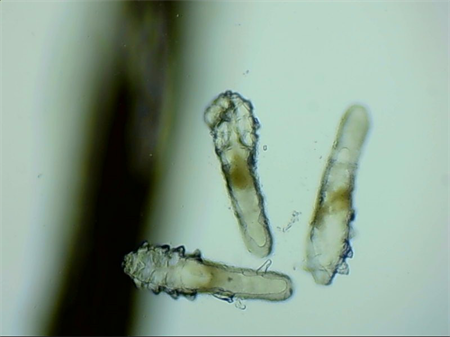

這就不得不提到眼科醫生經(jīng)常使用的螨蟲(chóng)檢測工具——螨蟲(chóng)鏡檢。它通過(guò)顯微利器,無(wú)死角全方位掃描你的睫毛,讓螨蟲(chóng)無(wú)處遁形。

▲螨蟲(chóng)鏡檢